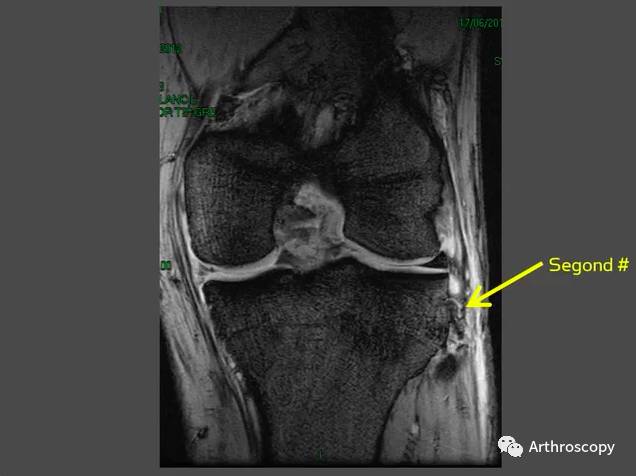

早在1879年,来自法国的DR.Segond发现,下肢过度的内翻加内旋暴力导致的胫骨平台前外侧撕脱骨折,常伴有前交叉韧带、内外侧半月板的损伤。这也就是我们现在经常讲到的Segond骨折👇。

5.在膝关节磁共振上可以看到相应的影像学证据。👇

因此,Arth君认为:在Segond骨折的前交叉损伤及术后重建前交叉韧带后有旋转不稳时,应考虑重建前外侧韧带。